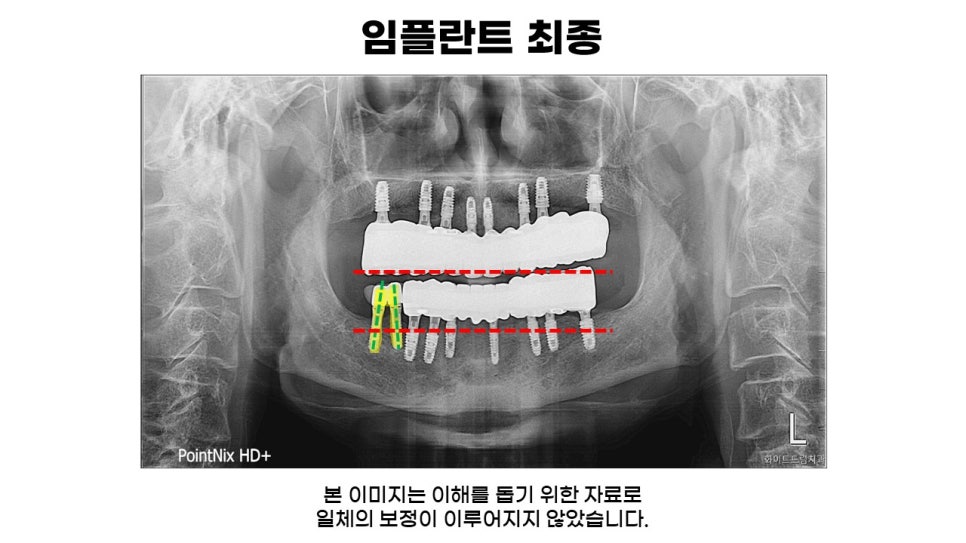

마지막으로, 하악 기존 임플란트를 제외한 나머지 치아와 상악 잔존 전치부 발치 후 치조골 이식을 동반한 임플란트 식립 후 최종 진단 결과물 입니다.

상악과 하악 모두 U자 형태를 그리며 잘 자리 잡았고, 교합상태도 또한 잘 맞아떨어짐을 확인할 수 있습니다.

무엇보다도 임플란트 식립 전 상태와 비교해 보았을 때 심미적인 부분이 크게 업그레이드 되었음이 확인 되실겁니다.